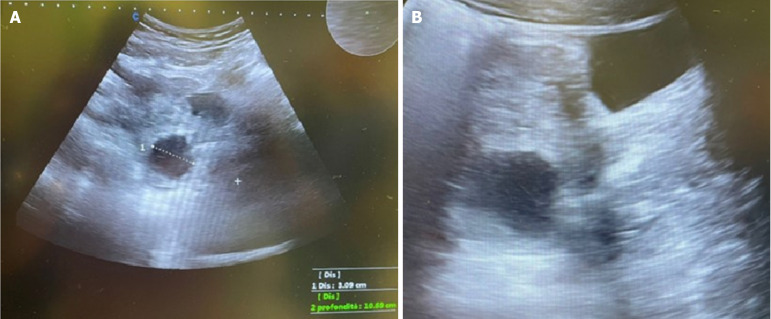

Case summary: A 13-year-old girl with acute gastrointestinal symptoms, such as vomit and abdominal and lumbar pains. Upon physical examination, the patient had localized abdominal pain in the left lower quadrant. Ultrasonography performed at the bedside revealed an enlarged left ovary with an irregular structure containing a 3 cm cyst. These findings raised suspicion of ovarian torsion. The child transferred to Gynecology Surgery Unit, where she was taken emergently to the operating room.